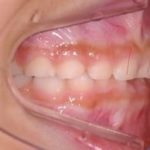

では左の写真のように、乳歯の後ろからおとなの歯が生えてきた場合はどうでしょうか?乳歯よりかなり後方から大きな永久歯が顔を出していますね。

その4にもありましたが、乳歯が抜けて、その場所に大きな永久歯が整列するにはスペースが明らかに不足しています。